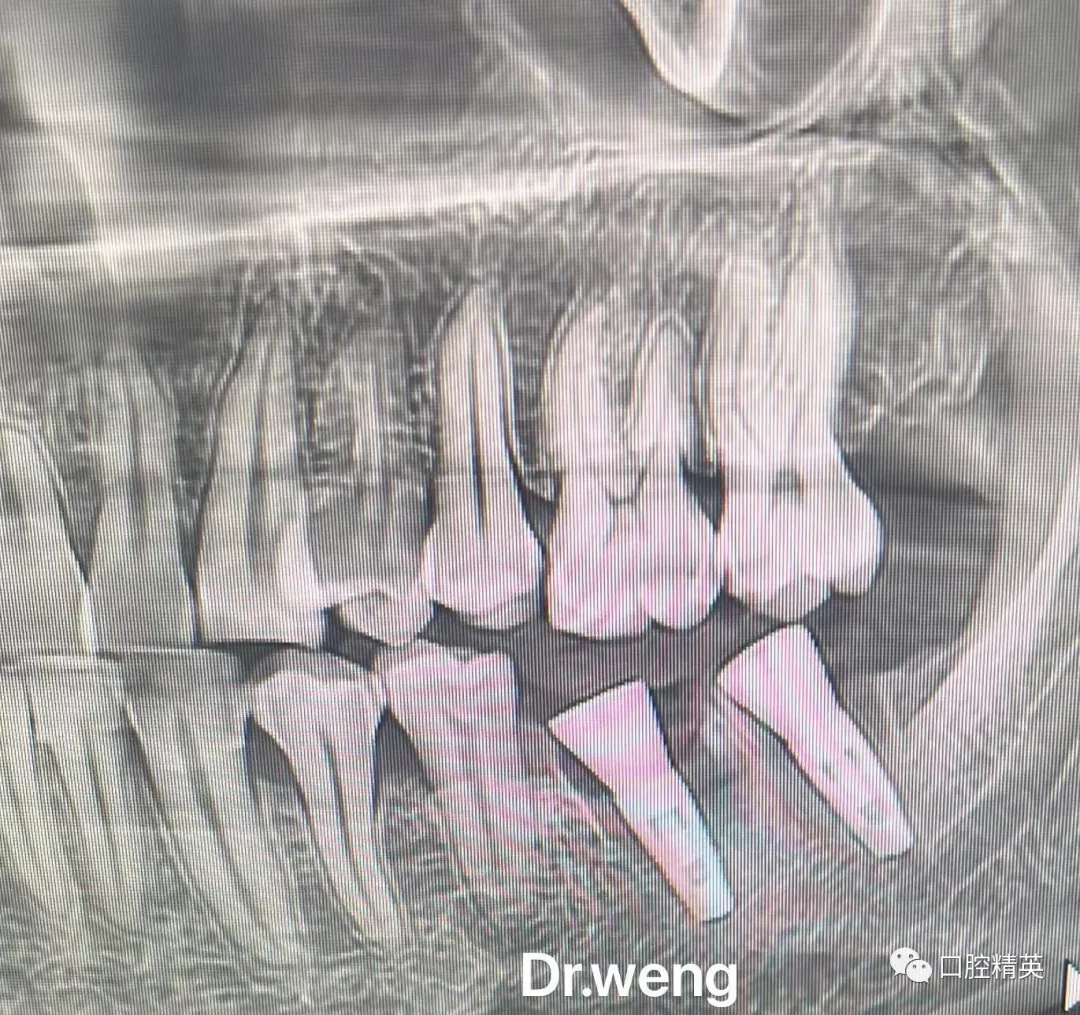

7、种植影像学分析;可以获得骨高度 ,骨宽度信息 ,甚至可以模拟种植体植入位点

11、精准种植;单颗前、后牙的理想植入位点